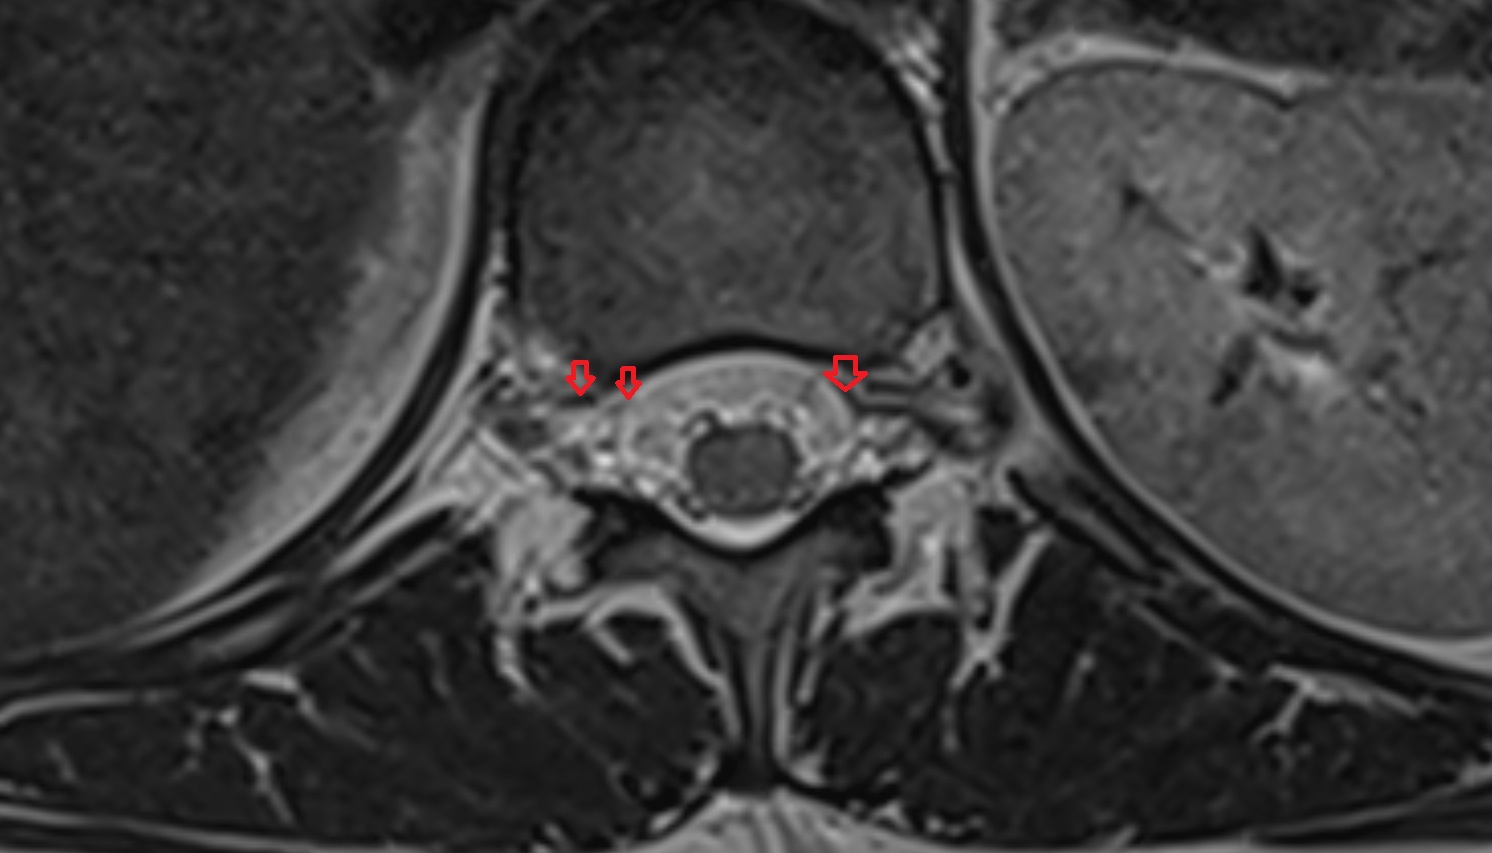

- Facet joint of vertebra (Zygapophyseal joints)

- Intervertebral Disc